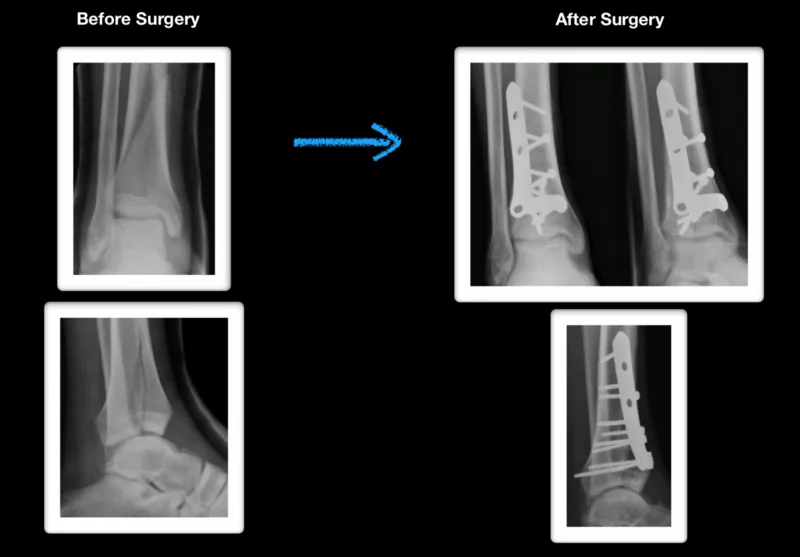

A Modified 2Stage Treatment for AO/OTA 43C1 Pilon Fractures Running After Pilon Fracture  A thorough examination for polytraumatic injuries, neurovascular status, and skin condition should be done. Physical therapy guidelines for ankle fracture with surgery. Pilon fractures are often severe injuries that can permanently affect the ankle joint. The intent of this protocol is to provide the clinician with a. A variety of approaches can be chosen based on fracture. A pilon fracture. Running After Pilon Fracture.

(AG). (A) Tibial pilon fracture type 43C2/AO; (B,C) Osteosynthesis by Running After Pilon Fracture  Pilon is the french word for pestle — an instrument used for crushing or pounding. A thorough examination for polytraumatic injuries, neurovascular status, and skin condition should be done. The intent of this protocol is to provide the clinician with a. A variety of approaches can be chosen based on fracture. Physical therapy guidelines for ankle fracture with surgery. Pilon. Running After Pilon Fracture.